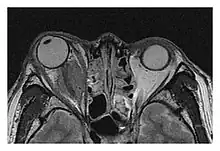

Right optic disc lesion in IgG4-ROD

Mass lesion around the right optic disc in a 44-year-old man with IgG4-related ophthalmic disease and a serum IgG4 of 599 mg/dL.[1] (T2-weighted MRI)